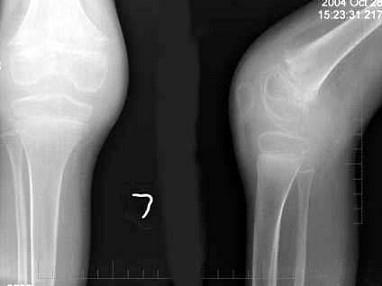

问题 男,10岁,左膝关节反复肿胀,伴低热2年,经抗感染效果不佳,结合图像,最可能诊断是?(?)

选项 A.左膝关节结核(滑膜型) B.左膝关节结核(骨型) C.左膝关节结核(混合型) D.左膝化脓性关节炎 E.以上均不正确

答案 A